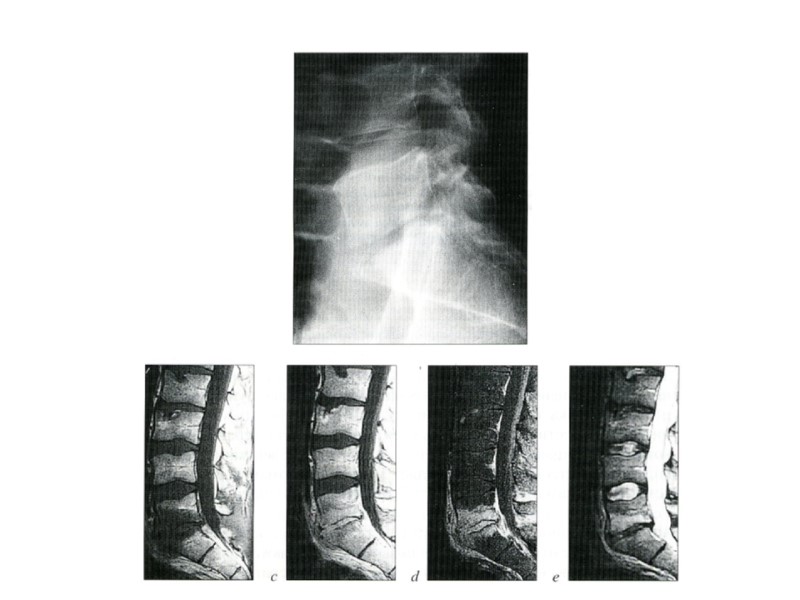

Рентгенограммы коленного сустава Сужение рентгеновской суставной щели Равномерное • Неравномерное Изменения суставов

Рентгенограмма области коленного сустава Склероз субхондральных пластинок

Рентгенограмма плечевого сустава Краевые костные разрастания

Рентгенограмма тазо-бедренного сустава Кистозные изменения при деформирующем артрозе